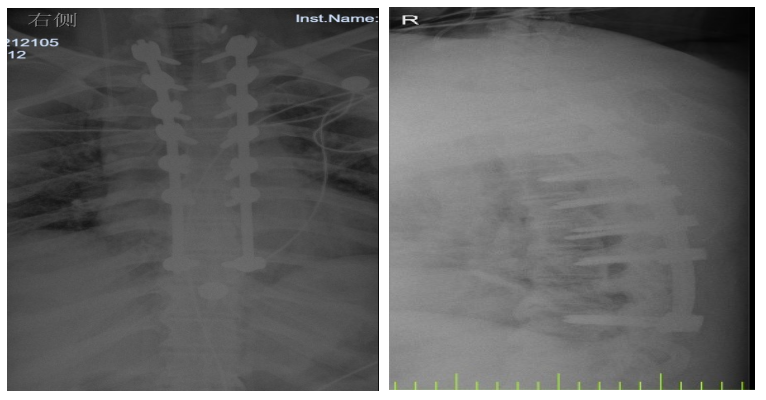

入院后,國文醫(yī)院骨科迅速組織多名專家會診,并為吳先生完善了頸椎及胸椎的 MRI 檢查。結(jié)果顯示,吳先生的頸椎及胸椎多階段嚴(yán)重椎管狹窄,脊髓壓迫超過 50%,情況十分危急。經(jīng)過骨科專家團(tuán)隊的綜合會診及評估,最終為他制定了一套個性化的治療方案,包括頸椎后路單開門椎管減壓頸椎融合內(nèi)固定術(shù),以及胸椎間盤切除伴椎管減壓胸椎植骨融合內(nèi)固定術(shù)。在完善術(shù)前檢查、確認(rèn)無手術(shù)禁忌后,骨科主任呂國福如期為吳先生實施了手術(shù)。

手術(shù)涉及頸椎及胸椎多個階段,操作難度極大。專家團(tuán)隊采用 “蠶食法” 減壓,分塊去除增生韌帶,最大程度減少對脊髓的損傷;同時運用椎弓根螺釘固定技術(shù),確保手術(shù)部位的穩(wěn)定性。

術(shù)后 3 天,吳先生的下肢肌力就從 3 級恢復(fù)到了 4 級;術(shù)后 1 個月,胸部束縛感明顯緩解;術(shù)后 3 個月,他已經(jīng)能夠重返工作崗位,生活基本恢復(fù)正常。